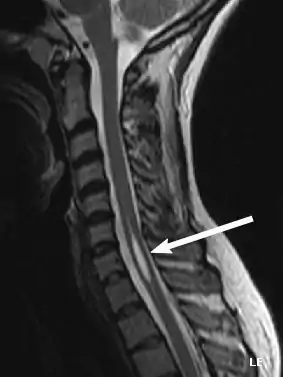

Physicians now use magnetic resonance imaging (MRI) to diagnose syringomyelia. The MRI radiographer takes images of body anatomy, such as the brain and spinal cord, in vivid detail. This test will show the syrinx in the spine or any other conditions, such as the presence of a tumor. MRI is safe, painless, and informative and has greatly improved the diagnosis of syringomyelia.[14][15][16][17][18][19][20][21][22][23][24][25]

The second major form of syringomyelia occurs as a complication of trauma, meningitis, hemorrhage, a tumor, or arachnoiditis. Here, the syrinx or cyst develops in a segment of the spinal cord damaged by one of these conditions. The syrinx then starts to expand. This is sometimes referred to as noncommunicating syringomyelia. Symptoms may appear months or even years after the initial injury, starting with pain, weakness, and sensory impairment originating at the site of trauma.

The possible causes are trauma, tumors, and congenital defects. It is most usually observed in the part of the spinal cord corresponding to the neck area. Symptoms are due to spinal cord damage and include pain, decreased sensation of touch, weakness, and loss of muscle tissue. The diagnosis is confirmed with a spinal CT, myelogram or MRI of the spinal cord. The cavity may be reduced by surgical decompression.